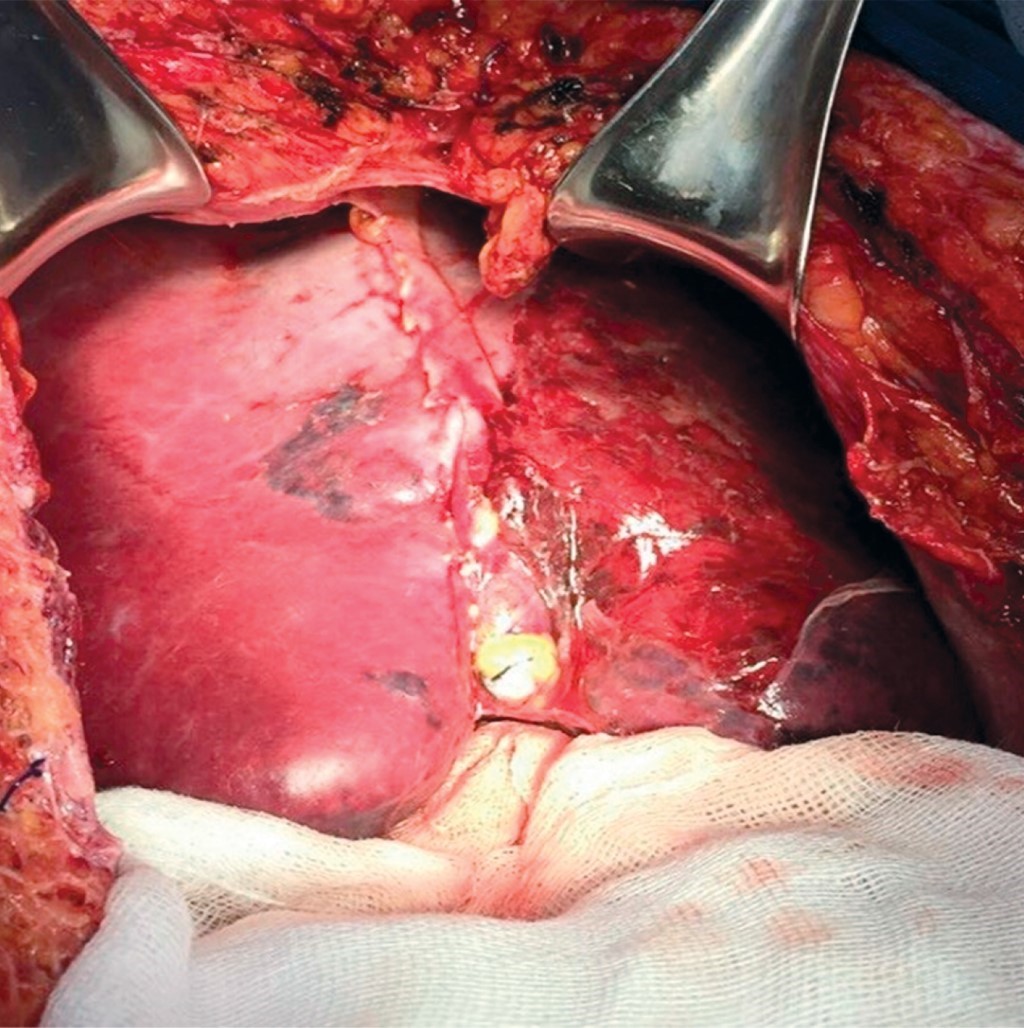

La paciente es trasladada a la Unidad de Cuidados Intensivos estable con presión arterial media de 70 mmHg, se realiza desempaquetamiento hepático a las 48 horas sin evidencia de sangrado activo, apreciándose hígado con adecuada consistencia, coloración, turgencia y con hematoma limitado (Figura 2). Veinticuatro horas después se retira el apoyo ventilatorio mecánico sin complicaciones, presentando adecuada evolución con tolerancia de la dieta, drenajes sin evidencia de sangrado activo; los exámenes de laboratorio a los siete días con hemoglobina de 11 g/dl, plaquetas de 332,000 y tiempos de coagulación dentro de parámetros normales, pruebas de funcionamiento hepático dentro de parámetros normales. Es egresada de la Unidad de Cuidados Intensivos estable, a los nueve días del postoperatorio presenta fiebre persistente, se realiza control tomográfico localizando amplia zona de necrosis en lóbulo hepático izquierdo y hematoma intraparenquimatoso de 15 x 10 centímetros (Figura 3), motivo por el cual se realiza nueva laparotomía exploradora con hallazgo de lóbulo hepático izquierdo necrótico y hematoma extenso de 1,500 ml (Figura 4); se realiza evacuación del hematoma, hepatectomía izquierda (Figura 5).